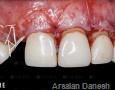

Surgery

1 Weeks

1 Months